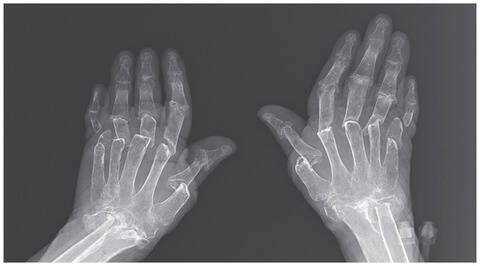

「指がどんどんちぢんでいく!」69歳女性のすり減る骨 トルコ

レントゲン写真に映し出された両手の骨は、破壊がかなり進んでいて、すべての指の第二関節が本来の位置からずれて脱臼しており、指の曲げ伸ばしができない状態だった。

サーティス医師は「破骨細胞の異常によって、急速に骨が溶けたために、指がめりこんでいる」と診断。骨が溶ける速さに追いつかなかった皮膚が、膝まで下げたズボンのように、ゆるゆると骨にまとわりついているほどだという。